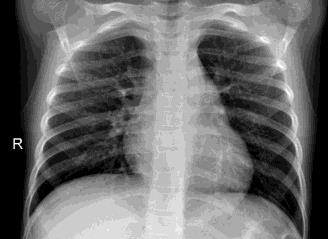

Pneumonia, a respiratory infection brought on by bacteria or viruses, affects a large number of people, especially in developing and impoverished countries where high levels of pollution, unclean living conditions, and overcrowding are frequently observed, along with insufficient medical infrastructure. Pleural effusion, a condition in which fluids fill the lung and complicate breathing, is brought on by pneumonia. Early detection of pneumonia is essential for ensuring curative care and boosting survival rates. The approach most usually used to diagnose pneumonia is chest X-ray imaging. The purpose of this work is to develop a method for the automatic diagnosis of bacterial and viral pneumonia in digital x-ray pictures. This article first presents the authors' technique, and then gives a comprehensive report on recent developments in the field of reliable diagnosis of pneumonia. In this study, here tuned a state-of-the-art deep convolutional neural network to classify plant diseases based on images and tested its performance. Deep learning architecture is compared empirically. VGG19, ResNet with 152v2, Resnext101, Seresnet152, Mobilenettv2, and DenseNet with 201 layers are among the architectures tested. Experiment data consists of two groups, sick and healthy X-ray pictures. To take appropriate action against plant diseases as soon as possible, rapid disease identification models are preferred. DenseNet201 has shown no overfitting or performance degradation in our experiments, and its accuracy tends to increase as the number of epochs increases. Further, DenseNet201 achieves state-of-the-art performance with a significantly a smaller number of parameters and within a reasonable computing time. This architecture outperforms the competition in terms of testing accuracy, scoring 95%. Each architecture was trained using Keras, using Theano as the backend.